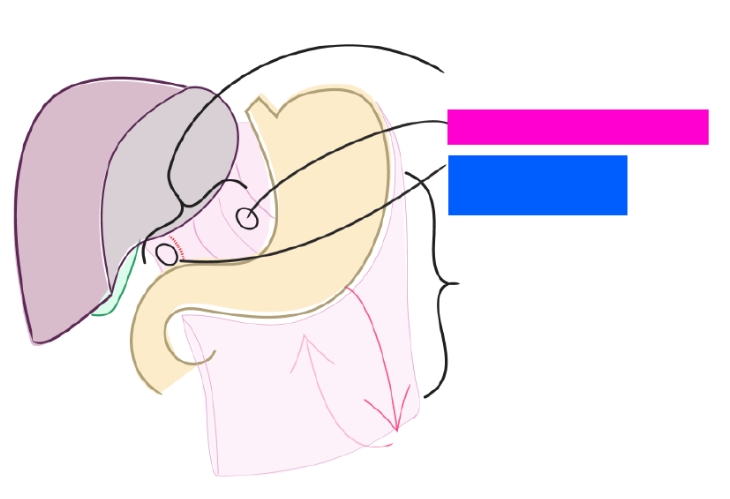

Esophagus

Diaphragm

Liver

Greater curvature of stomach

pink line

Lesser curvature of stomach

pink line

Lesser omentum

Hepatoduodenal ligament

blue box

Hepatogastric ligament

pink box

Greater omentum

Duodenum

blue highlight